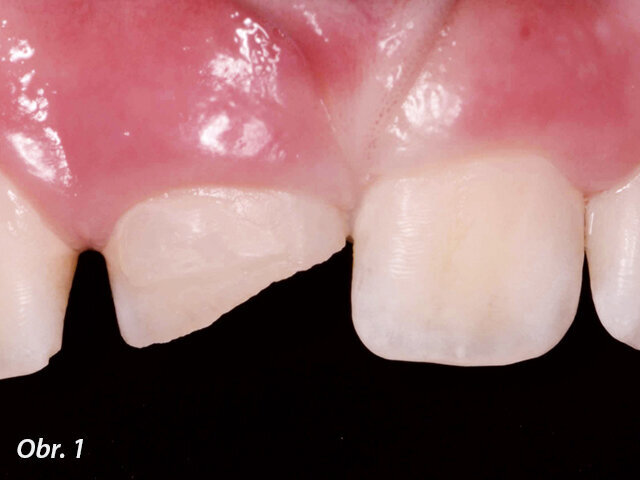

Při klinickém vyšetření nacházíme sanovaný smíšený chrup odpovídající věku pacienta. Zub 11 je poklepově a palpačně nebolestivý, parodontální sondáž je v mezích fyziologické normy. Z vestibulárního pohledu tvarově a velikostně odpovídá kontralaterálnímu zubu (obr. 1), z okluzního pohledu je vestibuloorální rozměr nepatrně větší než u zubu 21 (obr. 2). Šikmá fraktura zubu 11 má meziální okraj cca 1 mm nad okrajem marginální gingivy a distálně zasahuje do incizální třetiny klinické korunky. Dle diagnostického intraorálního rentgenového snímku je ukončen vývoj kořene s přítomným periapikálním nálezem a projasněním na meziálním aspektu kořene. Na ortoradiálním intraorálním rentgenovém snímku, ve srovnání se zubem 21 není jasně zřetelný průběh kořenového kanálku (obr. 3) a na excentrickém rentgenovém snímku je viditelný náznak kontury druhého kořene (obr. 4).